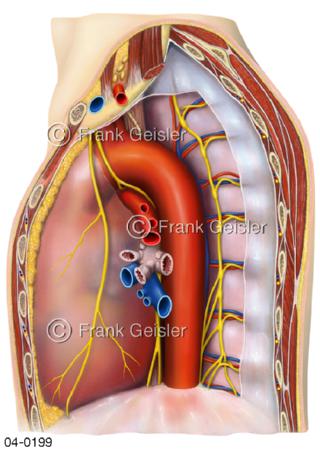

Bildergalerie Topografie Organe

Bilder zur topografischen Anatomie, die Lage der Organe und die Strukturen nach ihren räumlichen Lagebeziehungen zueinander, Übersicht der inneren Organe im Kopf und im Rumpf, Topografie der Organe im Brustraum (Thorax) und im Bauchraum (Abdomen)